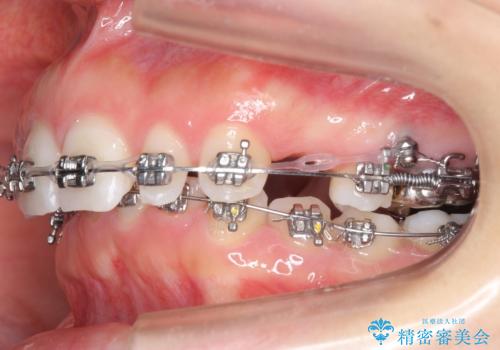

- 矯正装置

- メタル装置

- 治療計画

- 出っ歯を主訴に来院。

かみ合わせが深く、治療に時間がかかりました。

上顎2番は矮小歯だったのをセラミックで被せています。

- 矯正治療85万円 補綴治療16万円(emaxクラウン、仮歯)費用は治療当時の料金となります